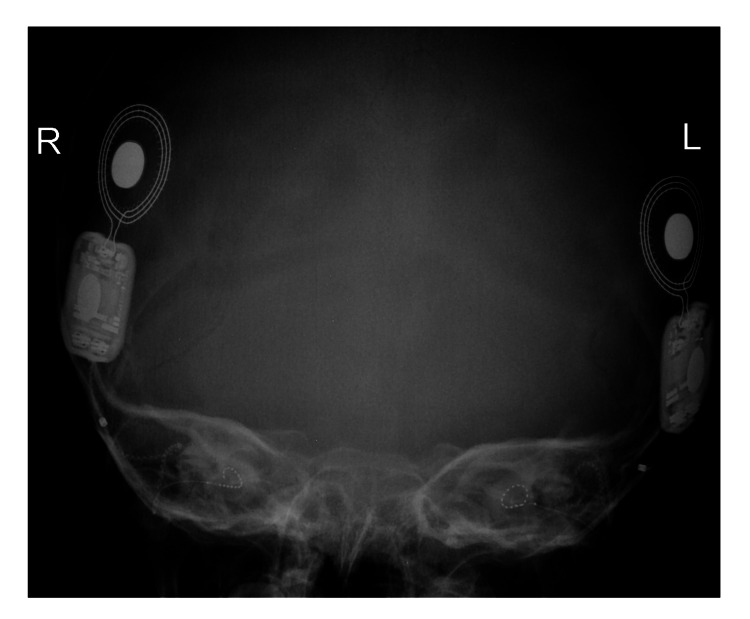

一名 14 个月大的女童,有全身发育迟缓、畸形特征(眼距过远、眼球突出、上睑下垂、小颌畸形)和弱视病史,被转诊至佳学基因遗传病罕见病基因检测案例协作单位。就诊原因是言语和语言发育迟缓。 她的父母是一级近亲,被诊断患有双侧重度至极度SNHL,并在 9 个月大时安装了双侧助听器。 然而,在随访中没有发现使用助听器有明显的好处。 磁共振成像 (MRI) 显示胼胝体完全发育不全(图 1)。 此外,全外显子组测序显示 LRP2 基因突变,证实了 DBS 的诊断。 在 18 个月大时,她的智商测试成绩为 75 分。

病例 1 的 MRI:(A) 矢状切面 (B) 冠状切面显示胼胝体完全发育不全